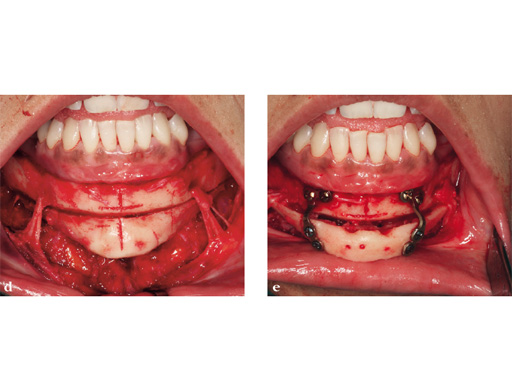

Case 1: A patient after multiple failed chin implants. Here piezosurgery proved to be superior to other oscillating instruments due to the controlled brush-type cutting motion, closeness to vulnerable structures which could be easily preserved, like the mental nerve on both sides, and protection of floor of the mouth vessels after completing the lingual corticotomy.

Case provided by Nils-Claudius Gellrich, Hannover, Germany